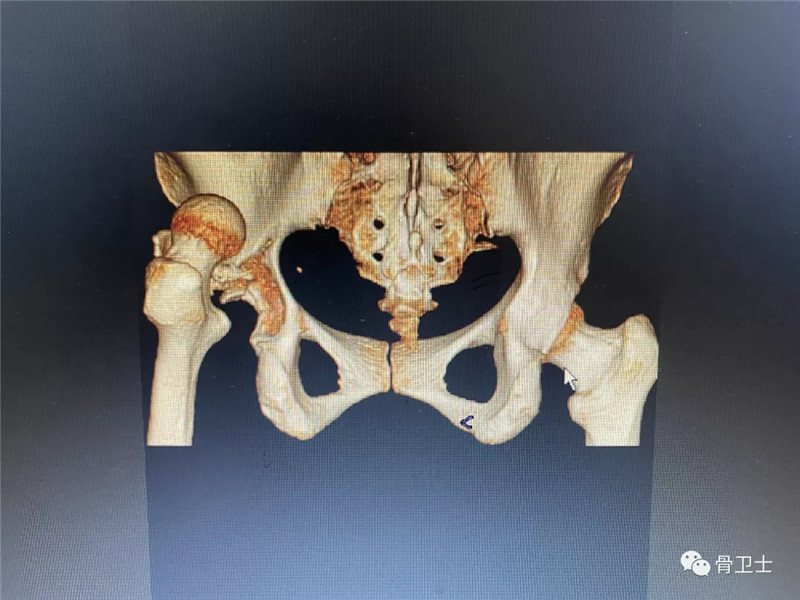

辅助检查:完善血型0型,Rh(D)血型阳性。2月22日,血常规示白细胞15.11X10^9/L、中性细胞比率90.51%,血象偏高,考虑创伤后体内应激反应所致;电解质常规检查:钾5.74mmol/L,嘱其低钾饮食,择期复查;肝功能常规:谷草转氨酶65U/L,考虑创伤所致,择期复查;血糖11. 82mmol/L,为餐后血糖,实属正常。新冠肺炎检查、肾功能示未见明显异常。心电图示窦性心动过速,电轴正常;头颅+胸部CT示未见明显外伤性异常;左髋关节正侧位片+左膝关节正侧位片示左髋臼粉碎性骨折,左股骨头脱位;左髋关节正侧位片+左膝关节正侧位片示左髋臼粉碎性骨折,左股骨头脱位;CT成套:双髋关节(CT重建):左侧可见粉碎性骨折、股骨头后脱位。

▲X光片